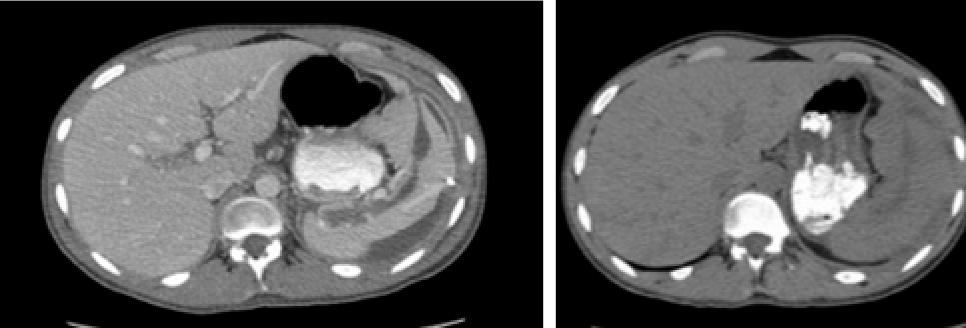

The chest x-ray showed only an elevated left hemidiaphragm (Figure 1). A CT of the abdomen with IV and PO contrast (Figures 2 and 3) showed a large (16 cm at its greatest dimension) nonsolid cystic mass within the spleen having a significant mass effect on the kidney, aorta, and stomach. The fluid measured 15 Hounsfield units (a much lower density than would be expected from blood)—suggesting a slightly proteinaceous source.

Figures 2 and 3. CT scan showing a large splenic cyst.